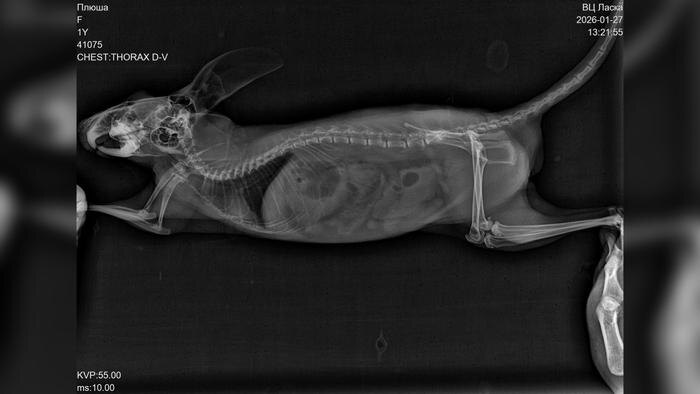

Пока хозяина не было дома грызун каким-то образом выбрался из своей клетки днём. Вечером Билан нашёл Плюшу возле музыкального оборудования, у неё была заметная рана на носу. Исполнитель немедленно связался с ветеринаром и получил инструкции по оказанию первой помощи, однако к утру состояние шиншиллы резко ухудшилось. Из-за сильного снегопада и пробок путь до клиники, находившейся в 60 километрах, занял почти два часа.

«За неё боролись около четырёх часов, но к сожалению, травмы оказались несовместимыми с жизнью. Диагноз — черепно-мозговая травма и отёк головного мозга», — написал он.

По словам Билана, он сначала предположил, что шиншилла могла получить травмы из-за кота Шахтёр, поскольку он хищник. Однако, по всей видимости, Плюша самостоятельно выбралась из клетки и с разбега врезалась в панорамное окно, что принесло тяжёлые травмы. Артист обратил внимание на то, как важно заранее понимать, с какими трудностями можно столкнуться, когда заводишь подобное животное.